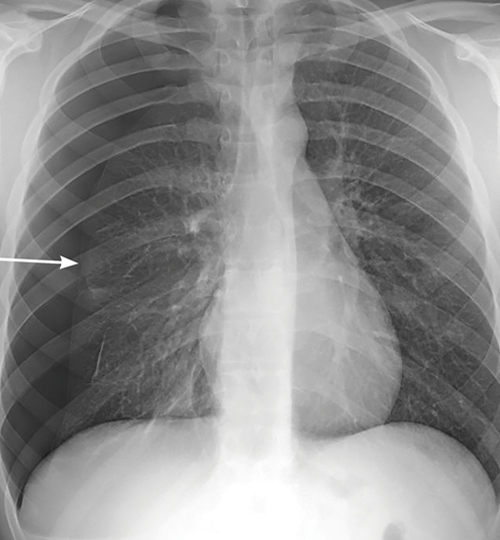

La radiographie thoracique (de face, debout et en inspiration ; clichés en expiration non recommandés) met en évidence une hyperclarté avasculaire plus ou moins importante délimitée en dedans par la plèvre viscérale visualisée par une ligne bordante pleurale. On parle de pneumothorax « complet » en cas de décollement sur toute la longueur de la ligne axillaire de l’apex au diaphragme.

On recherche des signes de compression avec déviation médiastinale et refoulement des organes, une bride retenant partiellement le poumon à la paroi (sa rupture peut provoquer un hémopneumothorax). Un pneumothorax est considéré de grande abondance lorsqu’il existe un décollement sur toute la hauteur de la ligne axillaire, d’une largeur ≥ 2 cm au niveau du hile.

En cas de pneumothorax spontané primaire récent (figure) :

• Si faible abondance et bonne tolérance : une prise en charge conservatrice est recommandée : surveillance ++ (recommandation forte), une résorption spontanée étant possible. La prise en charge doit être ambulatoire si le patient est observant, stable cliniquement et radiologiquement à 4 heures. Il ne doit pas être seul dans les 24 premières heures. Une consultation avec radiographie thoracique doit être prévue à 24-72 heures.